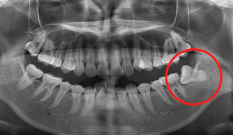

Case 07. 매복된 치아 & 쓰러진 어금니

영구치가 잘못된 방향으로 나거나 제때 올라오지 못하면 턱뼈 속에 갇히는 ‘매복 치아’가 생기며, 교정 치료로 올바른 방향으로 유도·견인해 정상교합 관계를 회복합니다.

어금니가 빠진 뒤 오랫동안 방치하면 인접 치아가 쓰러지고 맞물리던 치아가 내려오는데, 이 경우 쓰러진 어금니를 세우고 위치를 바로잡는 교정 치료로 씹는 힘과 치열의 균형을 되찾을 수 있습니다.

교정 치료 Before & After

• 매복된 치아

Before

After

• 쓰러진 어금니